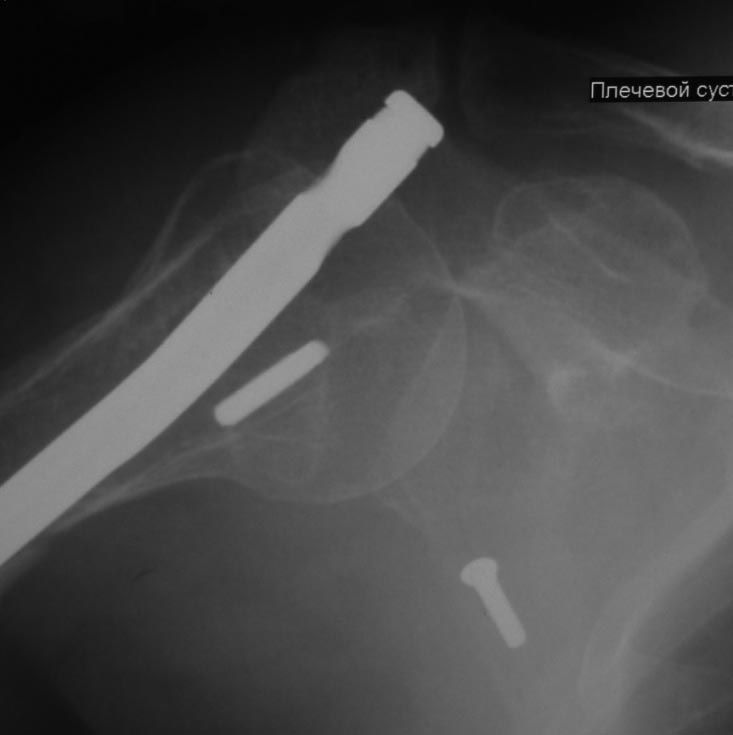

Как бы автор вопроса не убеждал себя, что в ситуации с гвоздем (его длиной, расположением относительно манжеты и бугорков и т.д.) все ясно, при таком качестве представленных рентгенограмм в единственной проекции никакой ясности быть не может.

В качестве примера - случай, который оперировал всего 2 недели назад, после похожего остеосинтеза, выполненного год назад. Пациентке 75 лет, тяжелый РА, легла для решения вопроса о ревизии тазобедренного сустава и заодно пожаловалась на то, что рука "крутиться" сама по себе, не поднимается. И болит, конечно. И посмотрите на разницу в информации на снимках головки плеча в двух противоположных проекциях. Даже комментировать ничего не нужно.